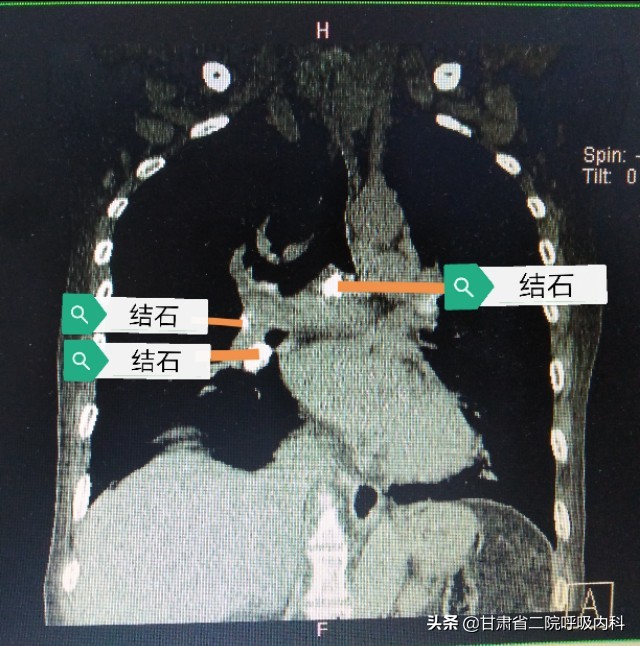

袁阿姨的气管结石左右主支气管都有,不仅数量多,而且非常大,手术中容易气管出血引起窒息,手术难度很大。呼吸内科柳小平团队在麻醉科的帮助下使用硬质气管镜历时1小时将袁阿姨的结石全部取出,手术顺利完成。袁阿姨术后马上觉着咳嗽明显减轻,呼吸都顺畅了。